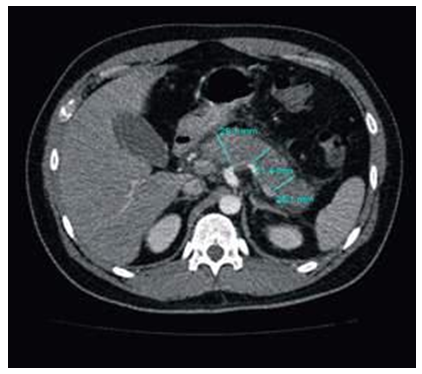

El tratamiento inicial consistió en ayuno, hidratación parenteral, analgesia, antiemético y protección gástrica. Estudios posteriores a las 48 y 72 horas revelaron la existencia de una marcada leucocitosis con neutrofilia y eosinofilia, perfil lipídico normal, un Ranson de 2, a la vez que no se reportaba la mejoría clínica esperada, debido a la persistencia del dolor y distensión abdominal con presencia de alza térmica; por esa razón se solicitó tomografía simple y contrastada dinámica de la región abdominal en busca de posibles complicaciones, el informe reportó un páncreas aumentado de tamaño, con bordes irregulares e infiltración de grasa peri pancreática (Baltazar C) (anexos, figura 2).

Páncreas con bordes discretamente irregulares, con incremento de tamaño a nivel de cabeza cuerpo y cola; infiltración de grasa peri pancreática (Baltazar C)